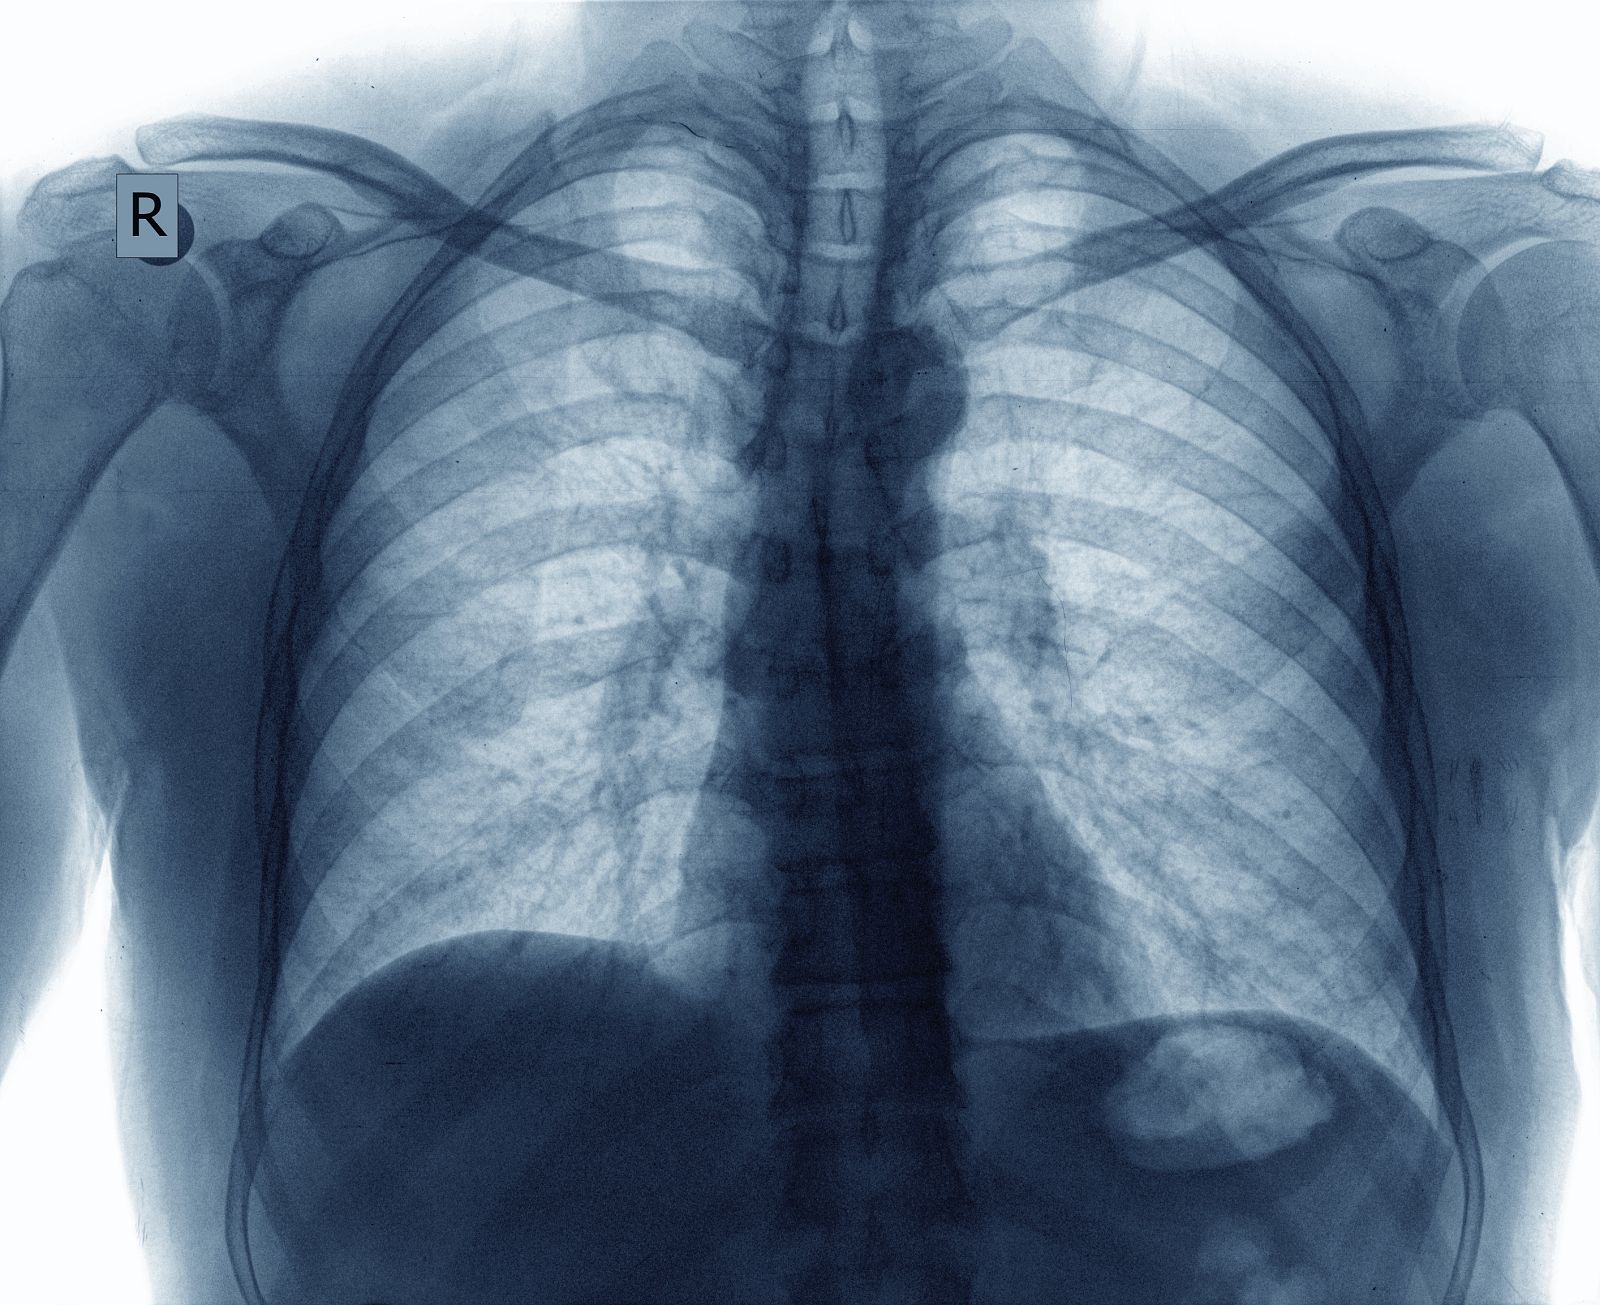

Radiografía de unos pulmones.